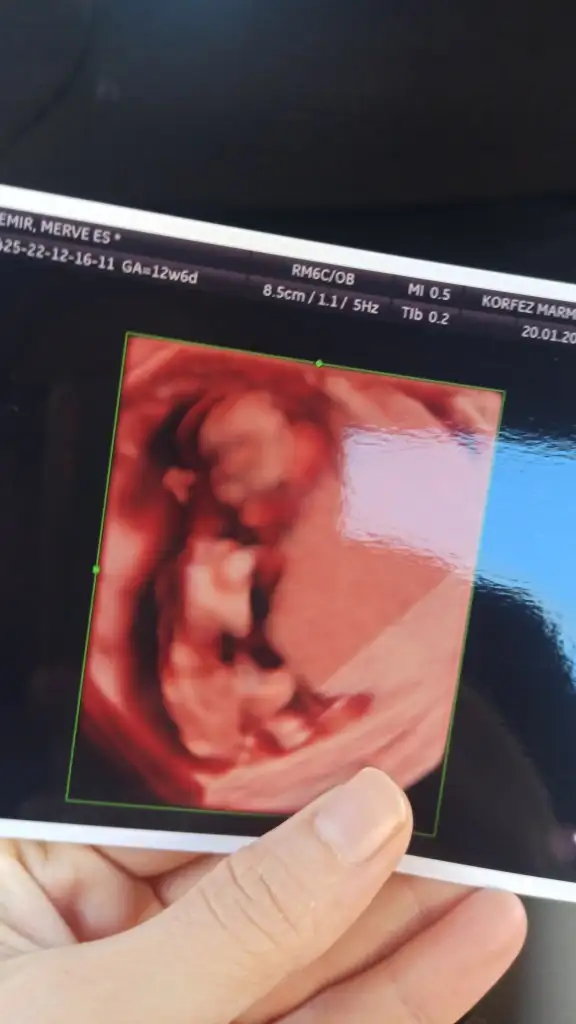

Benide.yorumlarmisinizzzz 12+6 renkli olanda diğerleri siyah olanlar 11+5 haftalıkBence kiz

Teşekkür ederim doktorumda yüzde 80 kız dedi bu hafta netleşicek. Sanırım nuba göre mi yorumladınız

Kafa yapısına skull teorisine göre cevapladım canım ben nubunu goremedimTeşekkür ederim doktorumda yüzde 80 kız dedi bu hafta netleşicek. Sanırım nuba göre mi yorumladınız